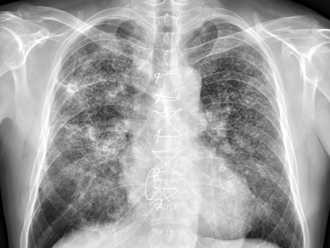

有時身體健康出問題,可能會透過明顯異狀表現出來。胸腔科醫師蘇一峰今(24)日分享,有位40歲不抽菸男子喘了好幾個月,就醫時他發現男子有明顯的杵狀指症狀,「幾乎十指手指都是杵狀指」,照了X光更不得了,「成千上萬顆肺結節,讓密集恐懼症的人頭皮發麻」,貼文曝光後引發熱議。

肺癌是國人頭號癌症殺手。胸腔內科醫師蘇一峰分享有名50歲婦人,因咳喘就醫,他檢查後認為婦人極可能罹患肺癌,要她快住院治療,婦人卻以請假恐會失業而拒絕,強調「家裡不能沒有這個工作」,看到這名生命已在倒數的婦人,仍在為生計打拚,讓他眼淚都快落下來。

一名30歲女護理師從不抽菸,也沒肺癌家族病史,但在某次健檢發現有一處需後續追蹤的毛玻璃結節,隔年再追蹤回檢,該病灶竟快速長大約去年2大小,進一步切片檢查,最終確診為肺癌。對於這樣的結果,該患者表示相當訝異,因從發現到確認罹癌期間,完全沒有出現任何不適症狀。